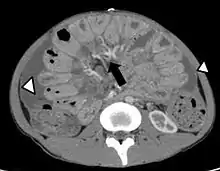

- échographie, scanner : non indiqués pour le diagnostic des péritonites, peuvent cependant apporter des renseignements quant à leur cause[6].